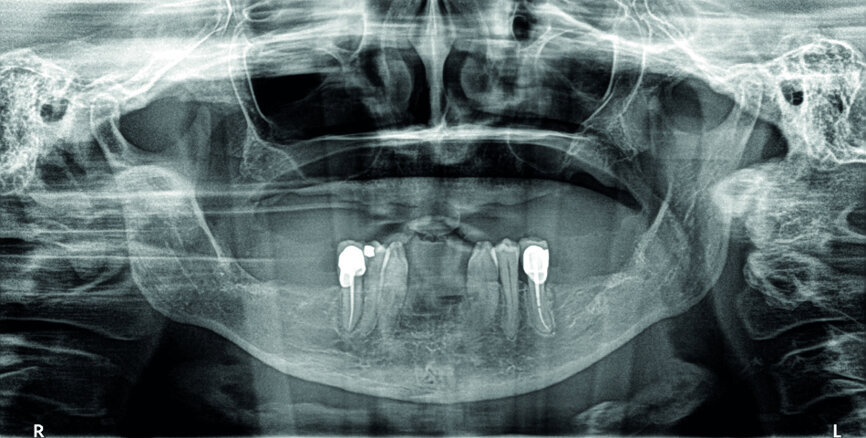

Cas 2 Indication pour une implantation bi-maxillaire. À la mandibule, préparation du lit receveur d’un implant à plaque, avec sa logette latérale vestibulaire

Cas 2b :Verrouillage de l’implant par insertion dans sa logette, et fixation à l’aide de 2 vis d’ostéosynthèse